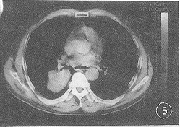

图5 右下肺低分化腺癌。瘤体可见深分叶,肿瘤细胞PCNA表达面积为12009.04 μm2

CT征象分叶征的形成与肿瘤各部份生长速度不均匀和肺支架结构的制约有关(图5)。本组资料有深分叶征者的PCNA表达面积明显高于无深分叶征者,深分叶征的出现是癌细胞增殖活跃明显的表现。以往影像一病理对照研究发现,CT图像瘤肺交界面的恶性征象包括棘状突起与毛刺征。棘状突起是在分叶基础上部分分化程度低,生长更快的肿瘤细胞亚群沿血管、支气管周围的结缔组织内浸润或沿淋巴管内蔓延导致肿瘤形态不均(图6)。有棘状突起的瘤体PCNA表达面积明显高于无棘状突起者,进一步证实了有棘状突起肿瘤的恶性生物学行为。而毛刺征的形成部分可能也为浸润生长所致,但主要是间质反应的表现[10]。本组资料显示有毛刺征者的PCNA表达面积与无毛刺征者之间无显著性差异(P>0.05),表明判断周围型肺癌浸润潜能、恶性度和预后方面,棘状突起价值较大。